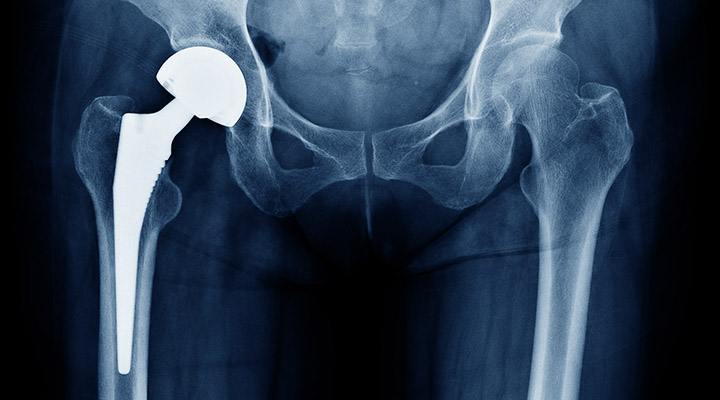

人工股関節置換術

人工股関節置換術は、傷んだ股関節の軟骨・骨を取り除き、骨盤側に人工の受け皿(カップ)、大腿骨側に人工の軸(ステム)と骨頭を入れて関節を置き換える手術です。痛みの原因となる関節面を人工物に置き換えることで、強い痛みを大きく軽減し、歩行や日常生活動作を改善することを目的とします。